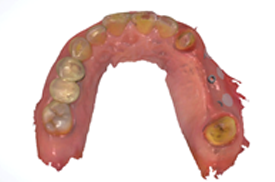

개별맞춤 수술유도장치

& 임시보철 제작

CT촬영과 구강스캔을 통해 이미지를 정합하고 3D 디지털로

보철디자인을 합니다. 또한 개별 맞춤형 수술 유도 장치를 디자인합니다.